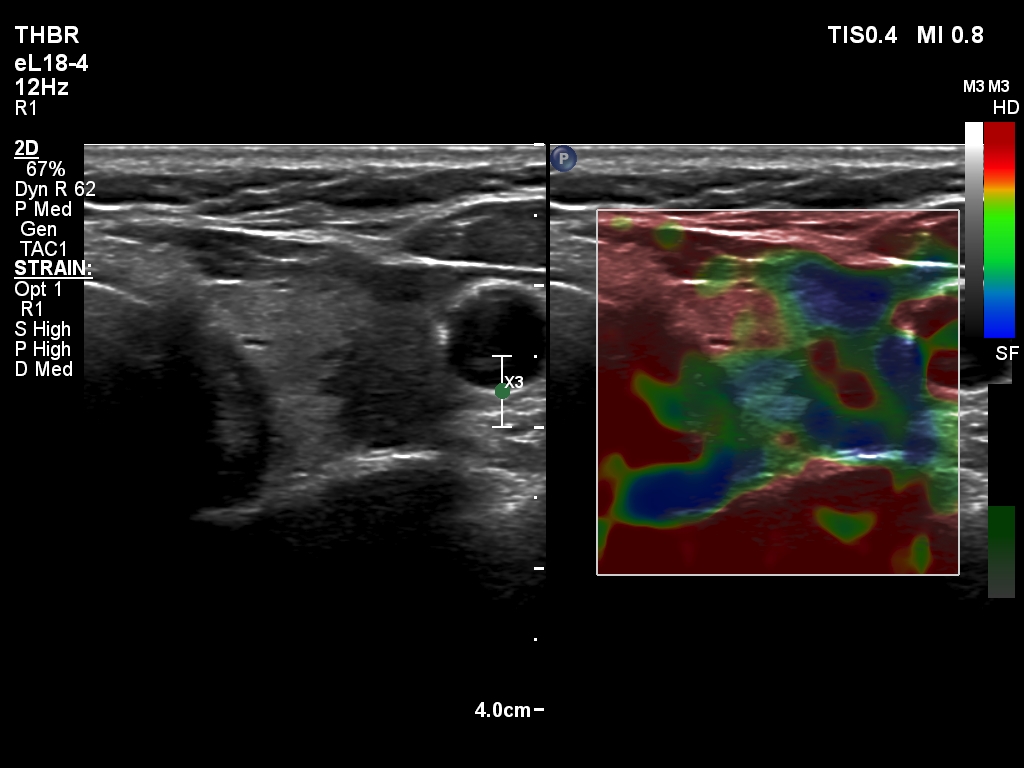

The composition of the nodule - case 2179 (ultrasonographic picture 20)

Right lobe, longitudinal scan

Upper part of the left lobe, transverse scan, elastography. This is a non-specific pattern.